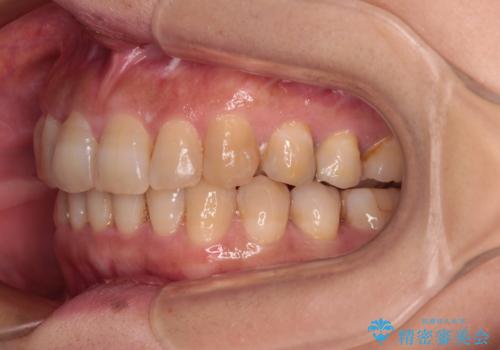

ディープバイトと前歯のデコボコ インビザラインによる矯正治療

- 前歯のディープバイトと叢生を気にして来院された患者様です。

目立ちにくい装置を希望されていたため、ワイヤー装置とインビザラインを提案したところ、インビザラインを希望されました。

下顎大臼歯が手前に倒れていたため、起き上がらせることで咬み合わせ高さを挙上し、ディープバイトと叢生を改善することとしました。